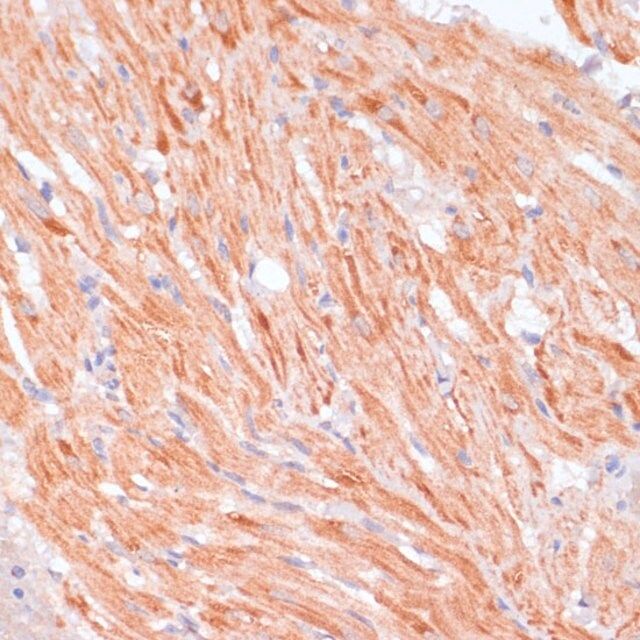

| technique(s) | immunofluorescence: 1:50-1:200 immunohistochemistry: 1:50-1:200 western blot: 1:500-1:2000 |